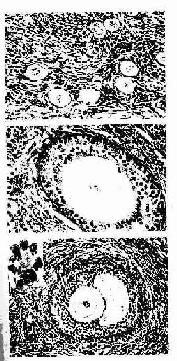

1.原始卵泡 原始卵泡(primordial follicle)位于皮质浅部,体积小,数量多(图17-2)。卵泡中央有一个初级卵母细胞(primary oocyte),周围为单层扁平的卵泡细胞(又称颗粒细胞)。初级卵母细胞圆形,较大,直径约40μm ,核大而圆,染色质细疏,着色浅,核仁大而明显,胞质嗜酸性。电镜下观察,胞质内除含有一般细胞器外,核周处有层状排列的滑面内质网(称环层板),并可见内质网与核膜相连,这可能与核和胞质间物质传递有关。初级卵母细胞是在胚胎时期由卵原细胞分裂分化液组成,随即进入第一次成熟分裂,并长期停滞于分裂前期(12~50年不等),直至排卵前才完成第一次成熟分裂。卵泡细胞较小,扁平形,细胞与外周结缔组织之间有薄层基膜。卵泡细胞具有支持和营养卵母细胞的作用,卵泡细胞与卵母细胞之间有许多缝隙连接。

2.初级卵泡 初级卵泡(primary follicle)由原始卵泡发育形成。此时期的初级卵母细胞体积增大,卵泡细胞由单层扁平变为立方形或柱状,随之细胞增殖成多层(5~6层)。在排列紧密的卵泡细胞间开始出现考尔-爱克斯诺小体(call-Exner body),其数量随卵泡的生长而增多(图17-2)。小体为圆形囊泡,腔面是一层基膜,周围紧密排列的卵泡细胞,腔内含有卵泡细胞分泌的物质,参与卵泡液的形成。卵巢颗粒细胞肿瘤与考尔-爱克斯诺小体的分化有关,在初级卵泡早期,卵母细胞和卵泡细胞之间出现一层含糖蛋白的嗜酸性膜,称为透明带(zona pellucida),它是卵泡细胞和初级卵母细胞共同分泌形成的。电镜下可见初级卵母细胞的微绒毛和卵泡细胞的突起伸入透明带(图17-3,17-4),卵泡细胞的长突起可穿越透明带与卵母细胞膜接触。在卵泡细胞与卵母细胞之间或卵泡细胞之间有许多缝隙连接。这些结构有利于卵泡细胞将营养物质输送给卵母细胞以及细胞间离子、激素和小分子物质的交换,沟通信息,协调功能。此外,在受精过程中,透明带对精子与卵细胞间的相互识别和特异性结合具有重要意义。随着初级卵泡的体积增大,卵泡渐向卵巢皮质深部移动。卵泡周的结缔组织梭形细胞逐渐密集形成卵泡膜,它与卵泡细胞之间隔以基膜。

图17-2 人卵巢HE ×160

A原始卵泡(↑) B初级卵泡 ↑示透明带

C次级卵泡 ↑示考尔- 爱克斯诺小体,左上角为该小体的高倍像

3.次级卵泡 初级卵继续生长成为次级卵泡(secondary follicle),卵泡体积更大,卵泡细胞增至6~12层,细胞间出现一些不规则的腔隙,并逐渐合并成一个半月形的腔,称为卵泡腔(follicullar antrum),腔内充满卵泡液(图17-2)。卵泡液是由卵泡细胞分泌和卵泡膜血管渗出液组成,卵泡液除含有一般营养成分外,还有卵泡分泌的类固醇激素和多种生物活性物质,对卵泡的发育成熟有重要影响。随着卵泡液的增多及卵泡腔扩大,卵母细胞居于卵泡的一侧,并与其周围的颗粒细胞一起突向卵泡腔,形成卵丘(cumulus oophorus)。此时初级卵母细胞直径可达125~150/μm。紧贴透明带的一层柱状卵泡细胞呈放射状排列,称放射冠(corona radiata)。分布在卵泡腔周边的卵泡细胞较小,构成卵泡壁,称为颗粒层(stratum granulosum)。在卵泡生长过程中,卵泡膜分化为内、外两层。内膜层(theca interna)含有较多的多边形或梭形的膜细胞(theca cell)及丰富的毛细血管,膜细胞具有分泌类固醇激素的结构特征。外膜层(theca externa)主要由结缔组织构成,胶原纤维较多,并含有平滑肌纤维。具有卵泡腔的次级卵泡和成熟卵泡又称为囊状卵泡。